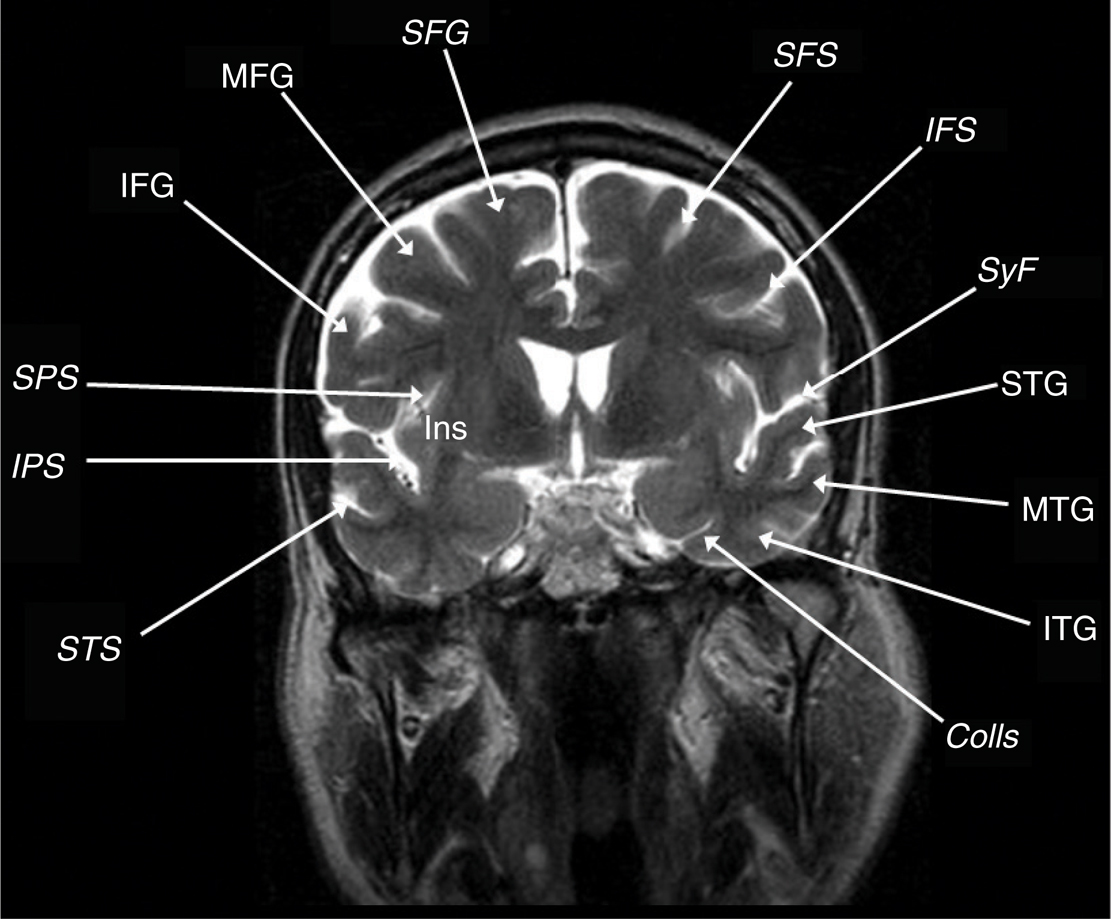

Awake language and motor mapping help reduce morbidity with insular tumor resections, especially on the dominant side (22). The Sylvian fissure is split and the superior and inferior peri-insular sulci provide dissection planes above and below the tumor, respectively. The lateral lenticulostriates define the medial resection plane but are sometimes hard to clearly identify or are obscured by the tumor bulk (22). The safe posterior border is the posterior limb of the internal capsule which may be identified by subcortical stimulation. On the dominant side, resection should not be taken posterior to any language sites. The tumor is resected piece-meal between the MCA perforators in a subpial fashion with sacrifice of small arteries supplying the tumor and insula. Subtle perturbations in motor or speech function truncate the resection at that point. With dominant hemisphere lesions, speech or motor problems may result from frontal or temporal opercular retraction, manipulation spasm of the MCA or interruption of the lateral lenticulostriate or opercular MCA branches, or injury to deep white matter tracts at the superior and medial aspects of the tumor (Figure 4). Nondominant hemisphere resections may have motor weakness through similar mechanisms even though motor function may not be consistently elicited by insula stimulation. With tumors involving the frontal or temporal opercula, a transopercular approach to the insula is a reasonable option (3).

Fig 4

Figure 4 Coronal T2-weighted MRI scan showing the superior frontal gyrus (SFG), middle frontal gyrus (MFG), inferior frontal gyrus (IFG), superior peri-insular sulcus (SPS), inferior peri-insular sulcus (IPS), superior frontal sulcus (SFS), inferior frontal sulcus (IFS), sylvian fissure (SyF), superior temporal gyrus (STG), superior temporal sulcus (STS), middle temporal gyrus (MTG), inferior temporal gyrus (ITG), and collateral sulcus (Colls).